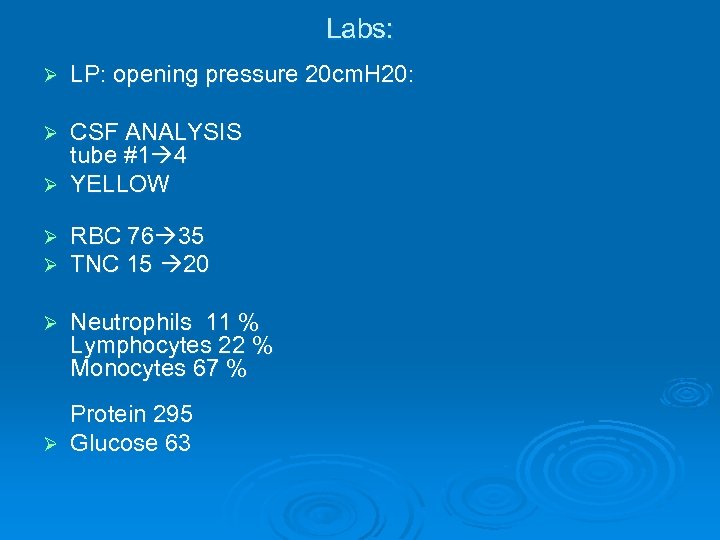

Labs: Ø LP: opening pressure 20 cm. H 20: CSF ANALYSIS tube #1 4 Ø YELLOW Ø Ø Ø RBC 76 35 TNC 15 20 Ø Neutrophils 11 % Lymphocytes 22 % Monocytes 67 % Protein 295 Ø Glucose 63